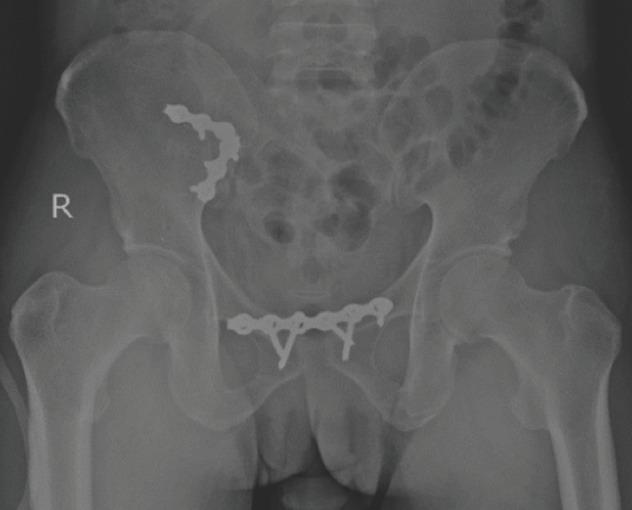

不稳定骨盆损伤中骶髂关节前路钢板固定的功能及影像学结果

Functional and Radiological Outcome of Anterior Plate Stabilisation of the Sacroiliac Joint in Unstable Pelvic Injury.

Sacroiliac joint disruption, resulting from high energy trauma can cause significant morbidity if no proper treatment given. Many techniques can be used to stabilise pelvic ring injuries. We studied the functional and radiological outcome following open reduction and anterior fixation of the sacroiliac joint and agreement between both outcomes.

MATERIAL AND METHODS

This retrospective study involved 15 patients with unstable pelvic injuries requiring surgical intervention from January 2015 to December 2020 who undergone anterior stabilisation of the sacroiliac joint. Radiological outcome assessments were done postoperatively by using Lindahl criteria. The complete functional outcome was assessed at least six months postoperatively when patients were able to weight bear by using Majeed system. Descriptive statistical analysis was performed using IBM SPSS Statistics Version 27.

RESULTS

The participants consist of 73.3% male and 26.7% female patients. A total of 66.7% of patients had a Tile type B pelvic ring injury, and the remaining 33.3% had a Tile type C pelvic ring injury. Based on the Majeed system, 73.3% of patients had excellent functional outcomes, and based on Lindahl criteria; there were 60% of patients who had excellent radiological outcome. However, there was no significant agreement between functional and radiological outcomes.

CONCLUSION

Definitive fixation of the sacroiliac joint by anterior plate stabilisation provided an excellent functional and radiological outcome mainly due to good anatomical reduction and mechanical stability. However, further study may be needed to evaluate the correlation between functional and radiological outcomes and compare the various method of fixation with a larger sample size.